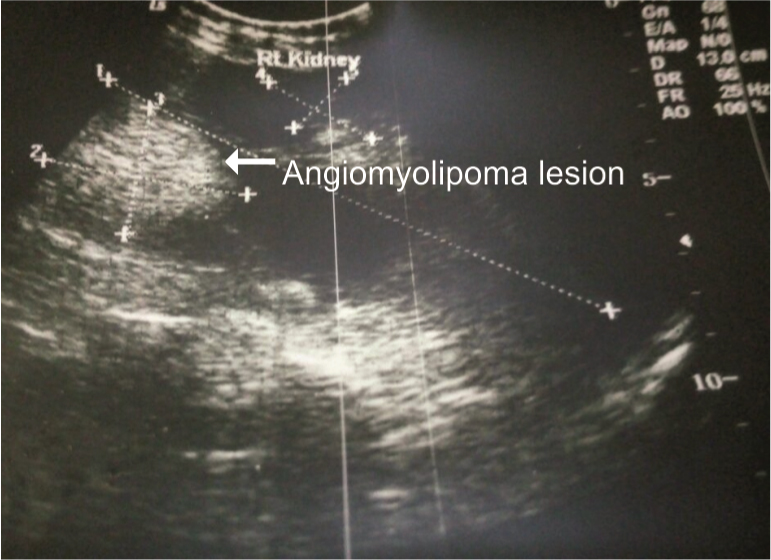

A 24-year-old second gravida female, with previous history of lower segment caesarean section for intrauterine growth retardation 2 years back, presented in OPD with two and half month of amenorrhea. She was known case of right sided congenital solitary kidney affected by angiomyolipoma, diagnosed incidentally 5 years back. Her previous postpartum period was uneventful. She had regular follow-up in Nephrology and Urology Department for renal angiomyolipoma. She was asymptomatic with haemoglobin 9.8gm%, WBC count 6300/cumm, platelet count 1,22,000/cumm, serum creatinine 0.62mg/dl, RBS 92mg/dl and normal urine routine and microscopy examination. Her obstetric ultrasound revealed single intrauterine live pregnancy with 10 weeks 3 days of gestation, with right ovary showing corpus luteal cyst and left ovary normal. Her Ultrasound Kidney Ureter Bladder (USG KUB) showed right kidney 15.1×7.3cm in size with normal echo pattern and preserved cortico-medullary differentiation [Table/Fig-1]. There was mild hydronephrosis, with multiple cysts in all poles largest measuring 4×3.2cm in size and multiple echogenic lesions of variable size largest 5.5×3.3cm. Left kidney was absent with normal urinary bladder. Patient was counselled about possible risks of spontaneous rupture of tumour leading to retroperitoneal haemorrhage, thromboembolism and possible management options in case of such emergency. But she continued her pregnancy with all due risks. Detailed anomaly scan was done and fetal 2D echo at 22 weeks of gestation were normal. She had regular antenatal follow- up monthly till 20 weeks, every fortnight till 28 weeks, thereafter weekly till term. Her serum creatinine, urinary albumin and renal ultrasonography were done twice monthly.

USG KUB showed right kidney affected by angiomyolipoma.